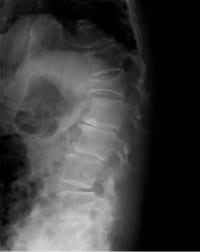

レントゲン

急性期単純X線像だけで腰椎椎間板の診断はできない。この疾患以外に、変形性脊椎症、腰椎圧迫骨折、腰部脊柱管狭窄症の示唆、悪性腫瘍の腰椎転移など鑑別の一助となりうる。慢性期になると、腰椎側画像で椎間板腔が狭小化している部位があれば、腰椎椎間板ヘルニア(L4/L5、あるいはL5/S1が多い)も疑われるが確定診断にはなりえない。

脊椎椎体の楔状変形の有無を確認する。